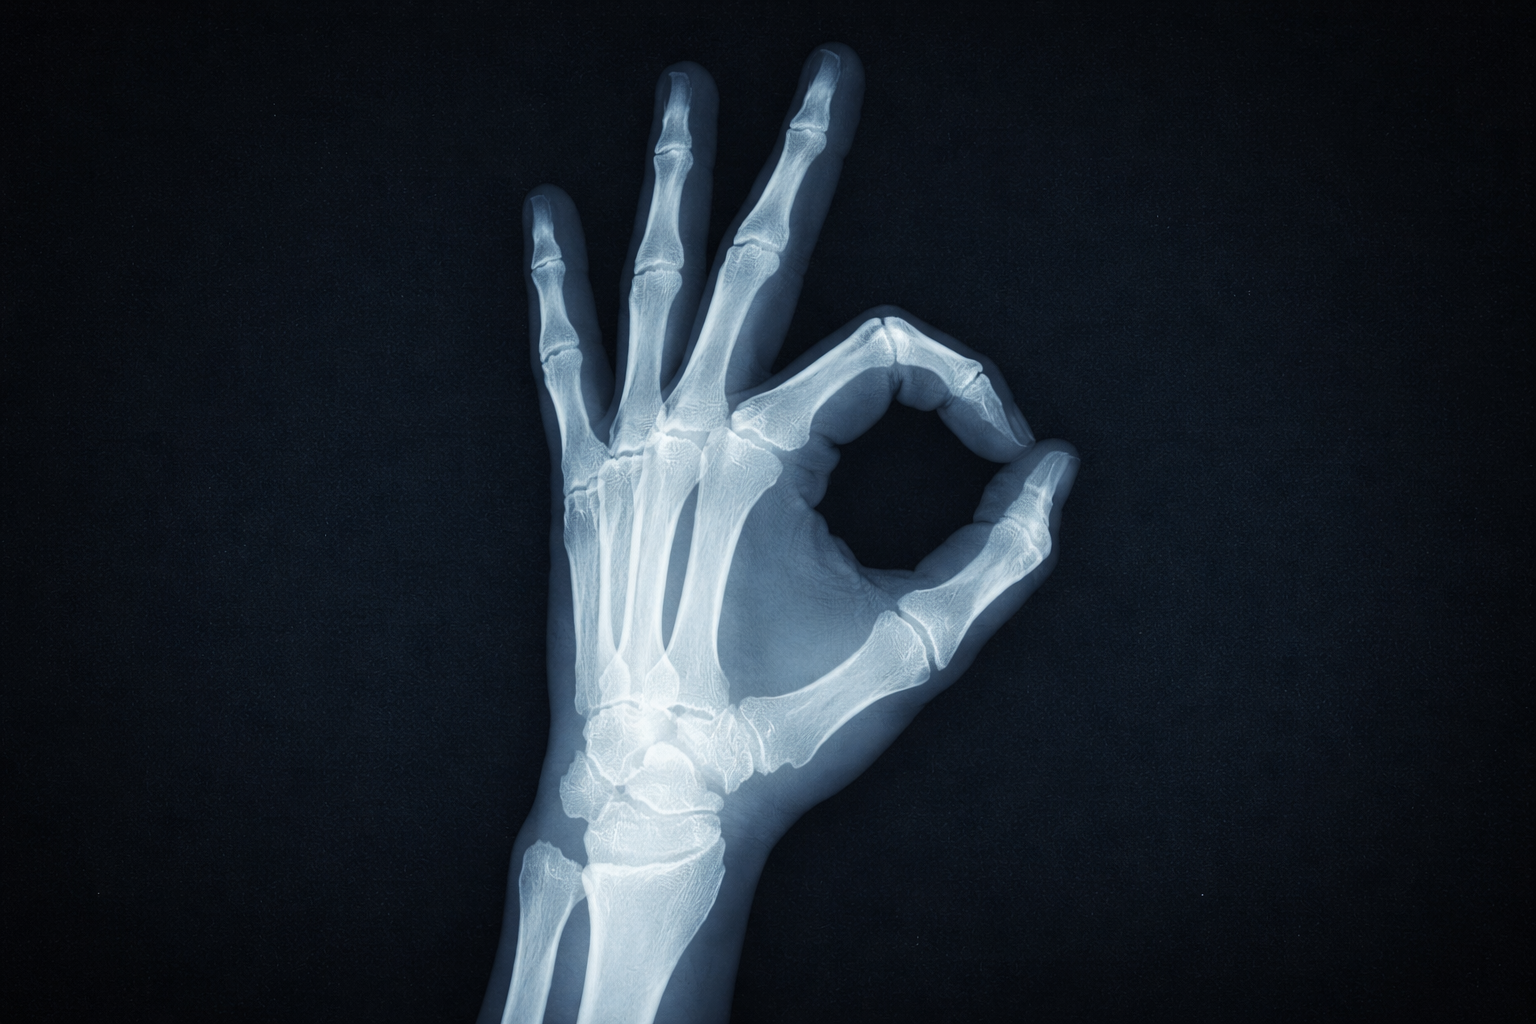

Травматология — это раздел медицины, занимающийся диагностикой, лечением и профилактикой травм и повреждений опорно-двигательной системы. Травмы могут быть вызваны различными факторами, такими как автомобильные аварии, падения, спортивные травмы и прочие несчастные случаи.

• Диагностика: точная диагностика травмы является первым шагом в правильном лечении. Это может включать рентгенографию, компьютерную томографию (КТ), магнитно-резонансную томографию (МРТ) и другие методы образования.